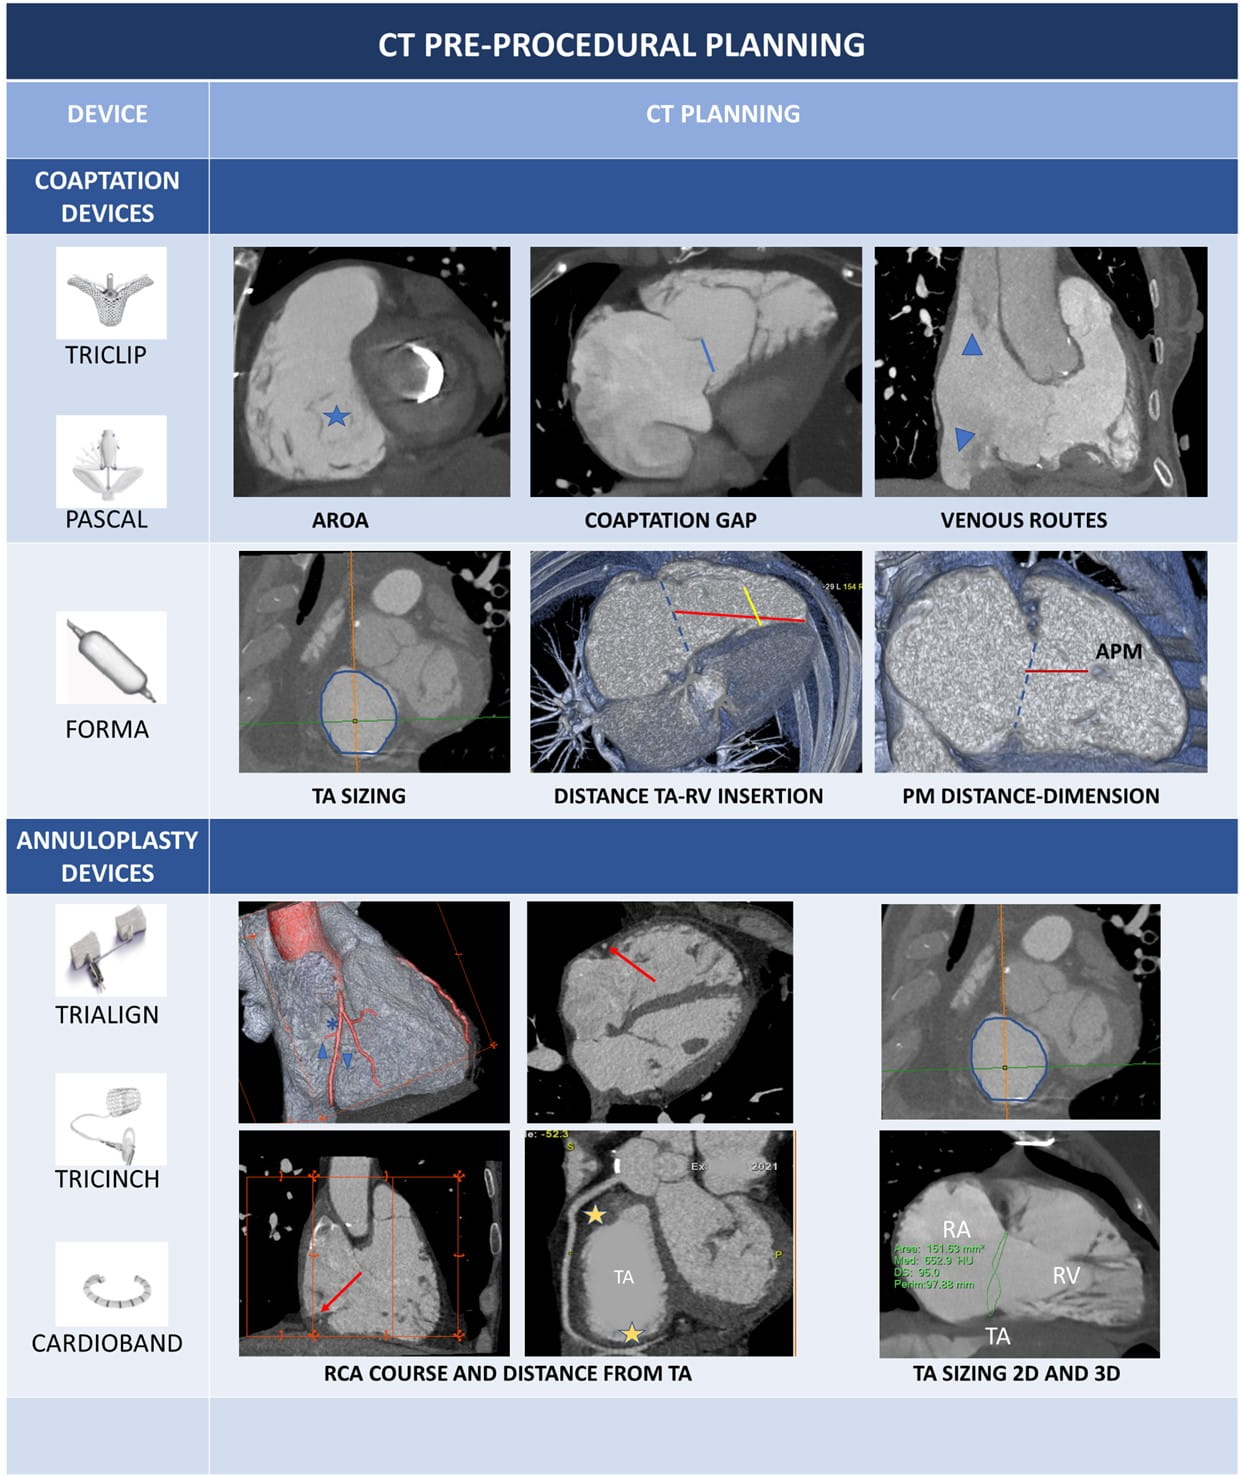

From an etiological point of view, TR can be classified into primary or secondary (Fig. 1).

Proper analysis of TR mechanism is the first step for an adequate definition of the patient’s diagnostic and therapeutic pathways.

TR can be divided into primary, secondary and CIED related [12]. The characterization of TR mechanism is based on a comprehensive imaging assessment of three elements: leaflet mobility, annular dimensions, type of RV and RA remodelling.

Primary or organic TR is caused by TV abnormalities and accounts for about 8% of TR [57].

Secondary or FTR is a consequence of right heart chambers remodelling, is the most common TR type and is differentiated into ventricular and atriogenic/atrial (or often defined as isolated TR). Ventricular secondary TR is caused by leaflet tethering and papillary muscle displacement, as a consequence of RV dysfunction and enlargement in conditions of volume overload or PH, generally secondary to left heart disease. Atrial secondary TR is characterized by annular dilatation and is related to AF, age, and HF with preserved EF [12, 50, 53]. Right ventricular and RA remodelling patterns in response to different pathological stimuli have been previously described.

Finally, implantation or extraction procedures of CIED in the RV leads may cause significant TR in 7–45% of cases with a plethora of mechanisms: leaflet impingement/adhesion/perforation/avulsion, chordal rupture/entanglement [12, 21]. When evaluating a CIED-related TR, a careful multi-view echocardiographic assessment of TR degree is pivotal, because an underestimation (more frequently with TTE) of the TR severity may occur with colour-Doppler due to acoustic impedance and reflectivity of the CIED leads [21]. 3D datasets of the TV are particularly useful to assess the transvalvular trajectory of the lead and its relationships with leaflets and the subvalvular apparatus. The transvalvular position of RV leads may be commissural, impinging on a leaflet, adherent to a leaflet or in the middle of the valve. Commissural and central trajectories are generally safe and not associated with significant TR. An adherent lead generally moves altogether with the leaflet and may cause TR only if it significantly interferes with the leaflet systolic closure. An impinging leaflet, instead, restricts the leaflet systolic closure and usually causes a significant TR [21].

In primary TR, the RA or RV can be normal or mildly dilated during the first phases of the disease; however, as TR begets TR, in long-standing primary TR, signs of volume overload may develop, with RA, RV and TA enlargement. In secondary TR, the mechanism of regurgitation in mainly related to RA or RV dilatation without primary leaflet abnormalities (see Fig. 5).

Fig. 5.Tricuspid regurgitation and RH chambers remodelling. In (A–D) primary TR are shown. Upper row (A,C,E,G) show diastolic images, while the lower row (B,D,F,H) systolic images. The black arrow indicates the TR regurgitant jets. Orange line: anterior/posterior leaflet; blue line: septal leaflet. Light green line: septolateral diameter of TA in diastole. Dotted green line: right atrium. Dotted yellow lines: RV walls dilatation. Primary TR is caused by leaflets abnormalities. A case of flail leaflet is shown in (A,B): right chambers can be normal or mildly dilated because of recent onset of TR; in Ebstein anomaly (C,D) the TR is caused by displacement of septal leaflet (blue line) with distortion of normal right chamber anatomy. Secondary TR can be atrial or ventricular mediated. In atrial functional TR there’s a prevalent enlargement of the basal wall of RV ((E), yellow dotted line), of the TA (light green line) and RA ((F), green dotted line). In ventricular functional TR, the RV is globally enlarged ((G), yellow dotted line) causing leaflets tenting (H). Abbreviations: RA, right atrium; RH, right heart; RV, TA, tricuspid annulus; TR, tricuspid regurgitation; TV, tricuspid valve.

Atrial and ventricular FTR have different CMR morphological features (Fig. 5). In atrial FTR, there is a severe TA, RA and basal RV dilation. A crucial feature of atrial FTR is the annular dilatation with increase of septum-to-lateral diameter, loss of TA saddle shape and presence of large central coaptation gap of the TV leaflets. This aspect of basal dilatation of RV, without elongation of the lateral wall and the trabeculated apex is called “conical deformation”. Ventricular FTR is usually associated with PH; the mechanism of TR is mainly due to papillary muscles displacement and leaflets tethering secondary to extreme right ventricular apex and lateral wall dilatation, while TA and RA dilation are less evident. In ventricular FTR the morphology of the RV becomes elliptical or spherical with less predominant basal enlargement as seen in atrial FTR [51].